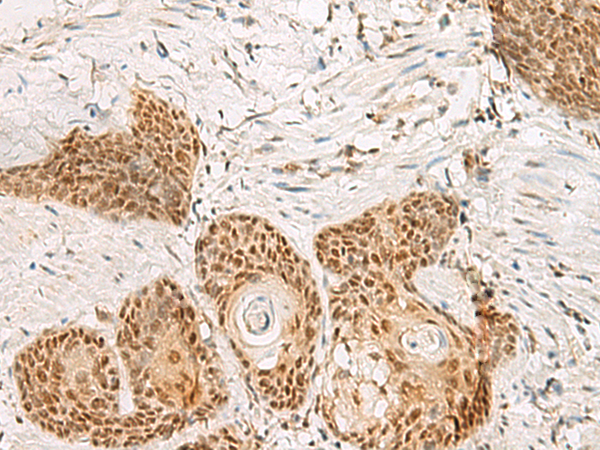

分类: 科研抗体货号: P09904别名: PSP1应用: IHC反应种属: Human, Mouse, Rat